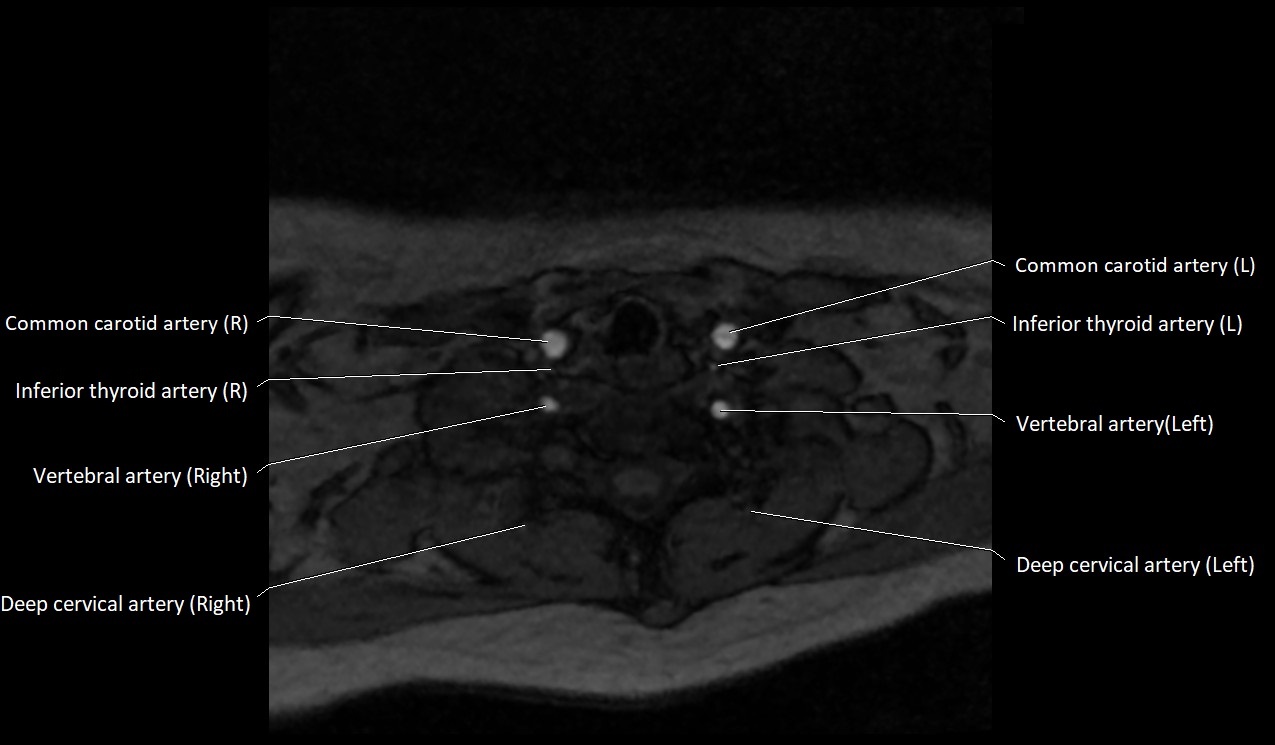

MRI images

image